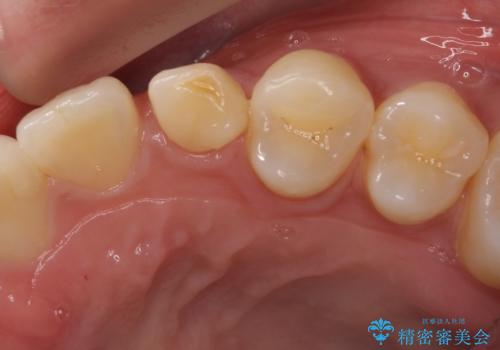

インプラントは、治療期間を短くすることが可能な、ストローマン社のSLActiveを使用することとしました。

インプラント治療は当初の狙い通り、矯正治療期間中に行い、スムーズに処置を進めることができました。